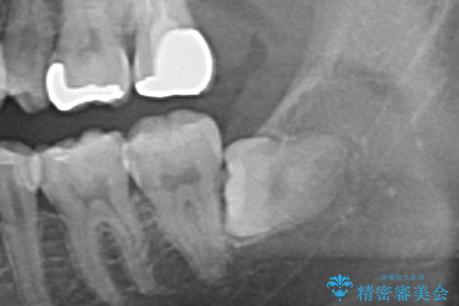

- 親知らずを抜きたいとのことで来院。

パノラマ写真(二次元的な写真)だと、下歯槽神経が近いかどうかわからないので

CT(三次元)を撮り、神経が近くないことを確認して抜歯を行いました。